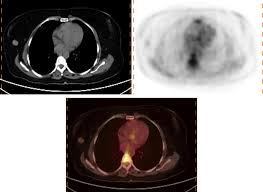

Pet/ct scans using axumin tracer, approved by fda last year and newly approved by medicare in some areas, are starting to be done at different locations. Pet scan for breast cancer a positron emission tomography (pet) scan is an imaging test that uses a radioactive substance (called a tracer) to look for potential spread of breast cancer. In a ct scan, you can see the broad pictures of all tissues and organs present in the body. However, the pet scan uncovers every unusual activity in the body and is more sensitive than any other existing imaging test. At left is a ct scan, while the center image is from a pet scanner.

The Clinical Utility Of Fdg Pet Ct In Follow Up And Restaging Of Breast Cancer Patients Sciencedirect from ars.els-cdn.com Pet scan is a type of test that may be used in cancer treatment. A ct scan produces multiple images, providing a detailed picture of the internal anatomy, including the location of cancerous growths. If you have a large breast cancer, your doctor may order a ct scan to assess whether or not the cancer has moved into the chest wall. This substance is often called a tracer, because it helps reveal cancer in the body. It is similar to a pet scan, but it uses a different radioactive substance that settles in areas of change in the bones. For cancer, pet is especially useful as it can scan the entire body and pinpoint both a primary tumor and areas of metastasis (where the cancer has spread). In some instances, cancers may not show on the scan. When breast cancer cancer spreads.

Is Radiation From A Ct Or Pet Scan Dangerous Cancer Ut Southwestern Medical Center from s3-us-west-2.amazonaws.com It is common for patients to receive a diagnosis for cancer of unknown primary. Pet scans can be useful for evaluating people after breast cancer has already been diagnosed, in a number of different ways: Types of cancer detected and treated. I am wondering, and never asked the oncologist about this. Bone scans, positron emission tomography (pet), and computed tomography (ct) all continue to be employed alone or in combination for the detection of breast cancers suspected to have spread. At left is a ct scan, while the center image is from a pet scanner. However, you may hear your doctor refer to this procedure just as a pet scan. Its supposed to be more sensitive/specific than naf and other older scans, and comparable i think to choline or acetate (lots of studies and info on the web) and.